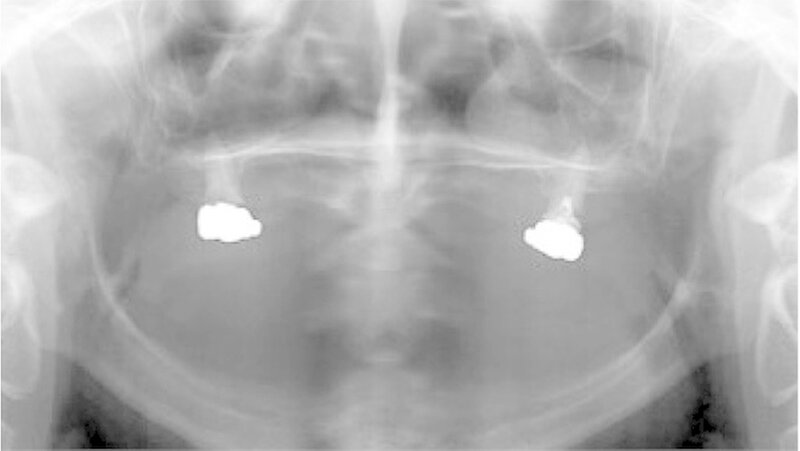

Bei dieser bei Behandlungsbeginn 16-jährigen Patientin waren seit Geburt nur die beiden ersten Molaren im Oberkiefer ausgebildet. Die Folge waren schmale und niedrige Alveolarkämme mit einem flachen Gaumengewölbe (Abb. 16 und 17). Die röntgenologische Abbildung bestätigte das geringe vertikale Knochenangebot. Eine Formanomalie der Zahnwurzeln ließ auf taurodonte Molaren schließen. Beide Molaren wiesen ausgedehnte kariöse Läsionen auf (Abb. 18).

Aufgrund des anatomisch sehr ungünstigen Prothesenlagers war der Erhalt der Restbezahnung im Oberkiefer anzustreben. Nach Kariesexkavation und Wurzelkanalbehandlung konnten beide Zähne mit einer Wurzelstiftkappe versorgt und die alten Prothesen entsprechend umgebaut werden. Im Anschluss an die Meisterabformungen und an die Ausrichtung der Wachswälle wurden die Modelle schädelbezogen einartikuliert, und die Prothesenzähne nach ästhetischen und funktionellen Richtlinien aufgestellt. Eine bilateral balancierte Okklusionsbeziehung konnte umgesetzt werden. Im Oberkiefer wurde eine gerüstverstärkte Totalprothese hergestellt, die auf den beiden Wurzelstiftkappen 16 und 26 verankert war. Im Unterkiefer konnte die Patientin mit einer Totalprothese versorgt werden (Abb. 21 bis 23).